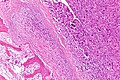

Template:Px Osteosarcoma. H&E stain. | |

| LM | cells with malignant features (e.g. nuclear membrane irregularities, marked nuclear size differences, mitoses) surrounded by delicate strands of osteoid |

- Cells with malignant features (e.g. nuclear membrane irregularities, marked nuclear size differences, mitoses) surrounded by delicate strands of osteoid.

- Osteoid on H&E: pink, homogenous, "glassy".

- Tumours typically very cellular - when compared to normal bone.

- +/-Large (multinucleated) osteoclast-like giant cells.[2]